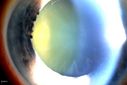

Pseudoexfoliation Ring437 viewsPatient's VA 20/50 with pinhole no improvement. Patient will have cataract surgery in the future. Notice Pseudoexfoliation ring centrally.     (0 votes)